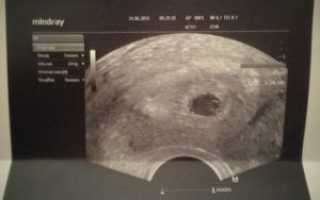

При трансвагинальном исследовании датчик вводят непосредственно во влагалище. Это позволяет получить наиболее точные результаты даже на самых ранних сроках.

Слишком малые размеры зародыша не позволяют сделать точную оценку его положения при обычном сканировании. Необходимо, чтобы датчик располагался как можно ближе к плодному яйцу. А это можно сделать именно при трансвагинальном ультразвуке, поэтому при ЭКО такой способ рекомендуют на самом первом исследовании.

2. Трансвагинальное исследование. В этом случае ультразвуковой датчик вводится непосредственно во влагалище. Рекомендуется проводить такую процедуру на начальных сроках беременности. Ведь эмбрион в этом периоде имеет очень малые размеры, и его очень трудно разглядеть при помощи обычного способа.

Для первого УЗИ используется только трансвагинальное исследование. Это связано с тем, что врач должен подробно рассмотреть зародыш, а также его расположение. Такой способ исследования крайне важен для повышения точности диагностики. В последующем врач может повторить трансвагинальное исследование, а в дальнейшем – делать только трансабдоминальное.